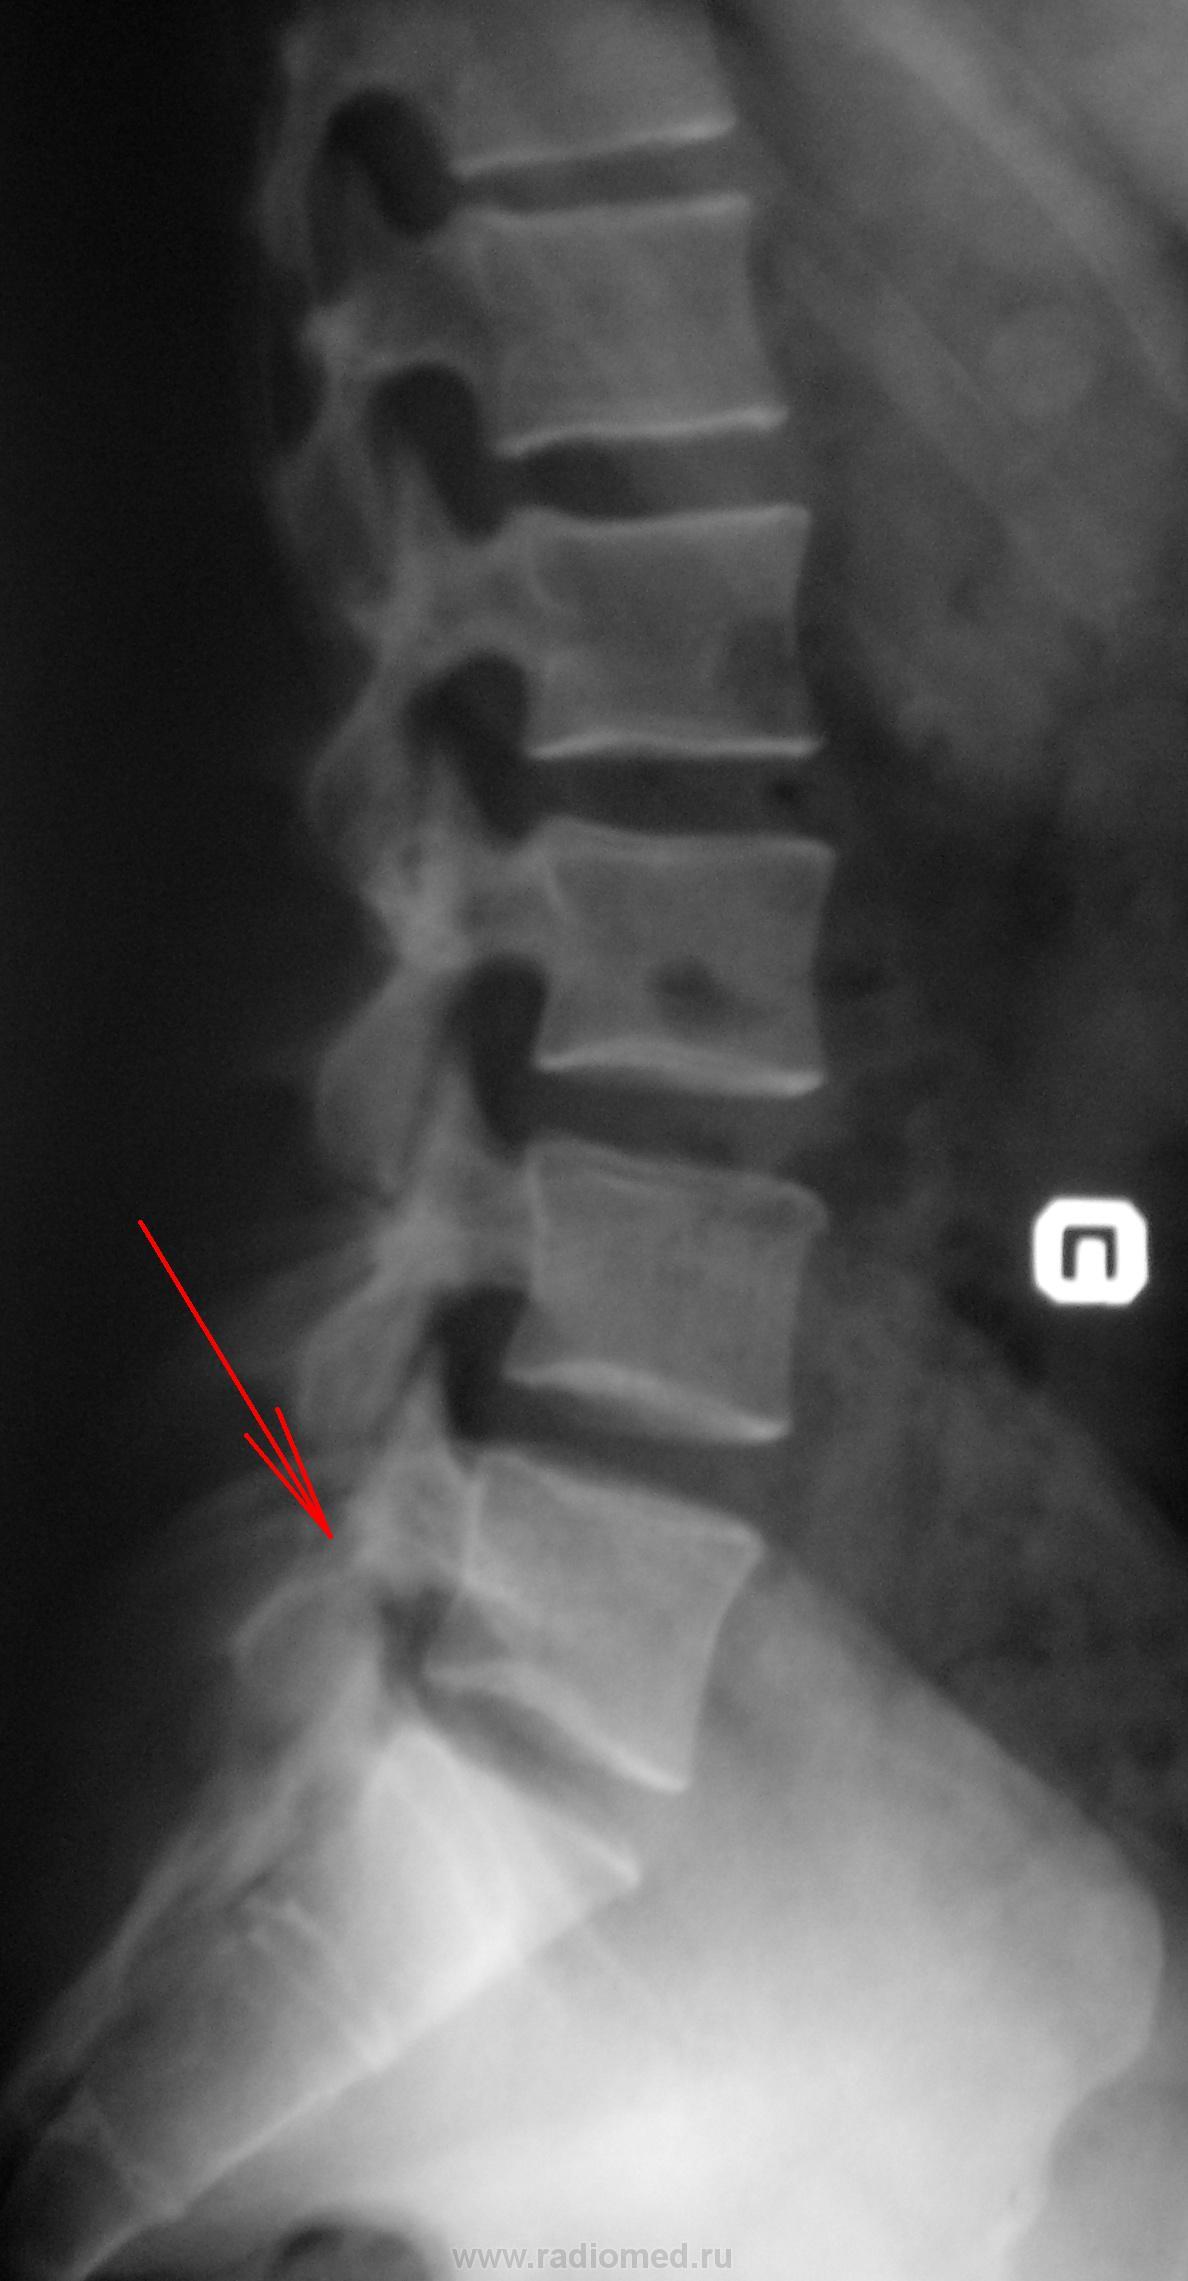

Случай №1 Мужчина, 40 лет указательным пальцем указывает на болезненность L5 Сделали снимок после консультации у невропатолога. На прямой проекции снимок немного подвёрнут, показалась щель межпозвонкового сустава, по своим контурам похожая на артроз. В боковой проекции определяется (на мой взгляд) щель в дужке позвонка между суставными отростками. Так ли это? Боли то именно у него здесь. Ещё похоже что-то есть в желчном или в почках(камни). Ваше мнение уважаемые коллеги?

1. Аномалия тропизма правой суставной пары L5-S1, сглаженность лордоза

Случай №1. Аномалия тропизма согласен. А для исключения сподилолиза назначить функциональные пробы.